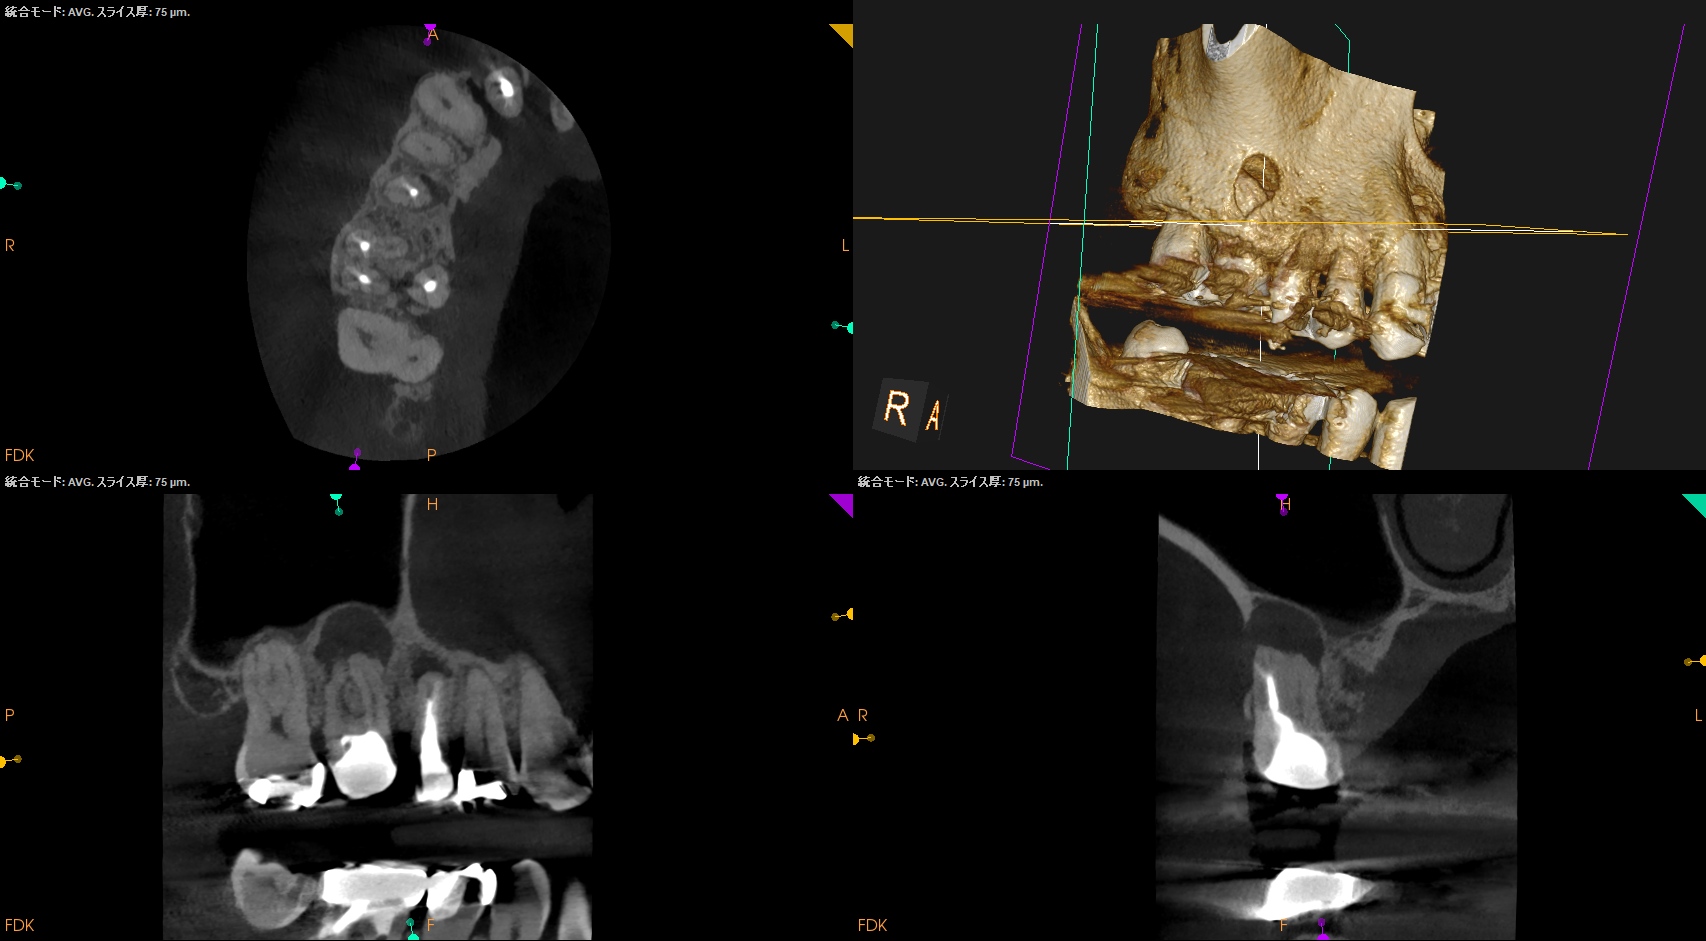

CBCT(2025.9.22)

#4

#3 MB

DB

P

これで抜歯とは…意味がわからない。

このCBCTの絵でこの結果が想像できるだろうか?

このことから何が言えるか?と言えば、

CBCT画像からのみ根尖部の解剖学的形態・状態を推し量るのは無理である

という臨床的事実だ。

再根管治療は実際にFileを根管の中に入れないとそれに意味があるかどうか?はわからないのである。